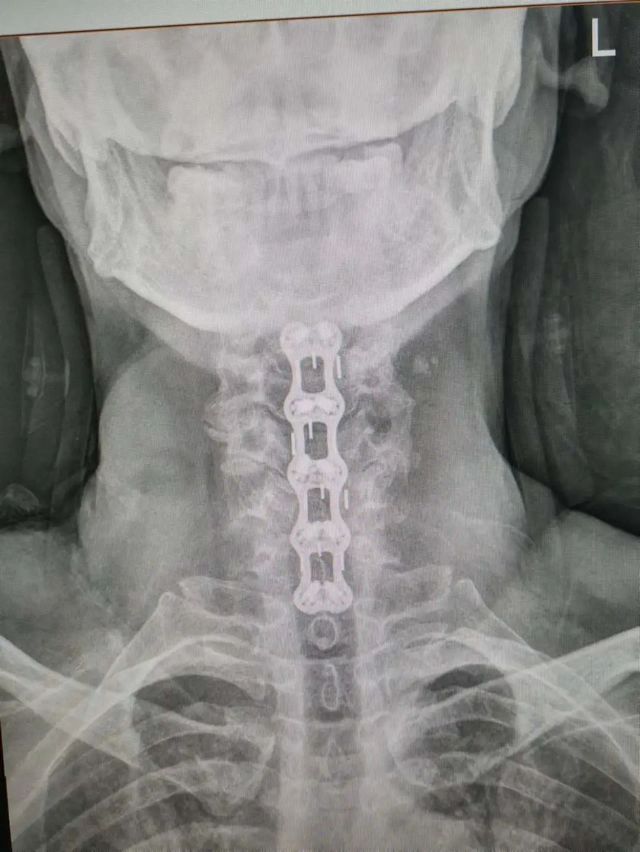

杨先生术后拍片

由于杨先生的病情严重,需住院治疗。杨先生入院后,泸州市中医医院骨伤二科科主任杨陈一制定了手术计划,决定脊髓型颈椎病的手术从前路切开减压,颈3/4 、颈4/5、 颈5/6、 颈6/7椎间盘切除,椎间融合,钢板内固定术手术,而腰椎管狭窄症经后路切开减压,腰3/4、腰4/5椎同盘动除,椎间融合、钉棒系统内固定术。